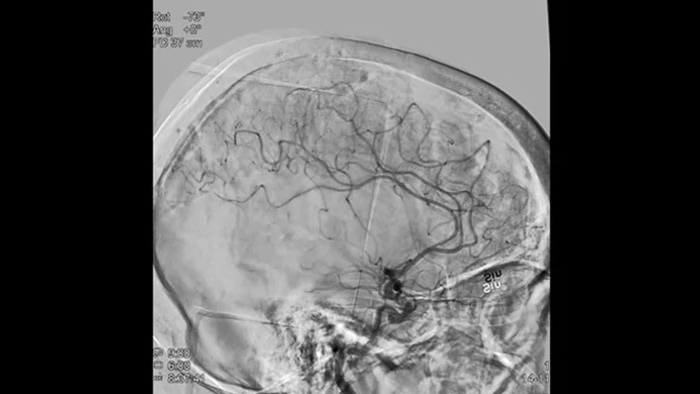

O ClarityIQ aplica uma Compensação Automática de Movimento durante a ASD em tempo real para manter imagens nítidas dos vasos, facilitando uma tomada de decisão confiante ao longo dos procedimentos de AVC.

O Roteiro SmartCT fornece referências anatômicas para facilitar a navegação precisa do fio guia, do cateter e do dispositivo até o coágulo.

As visualizações de ASD de alta qualidade permitem avaliar se você recuperou o coágulo inteiro e se pedaços do coágulo foram dispersados distalmente no cérebro. Você pode confirmar a restauração do fluxo sanguíneo para a penumbra e verificar se há sangramentos periprocedimento.

Tome decisões bem-fundamentadas quanto a se o coágulo pode ser alcançado e qual rota utilizar. O Roadmap Pro, um roteiro avançado de duplo contraste, ajuda a aprimorar a visualização de vasos superpostos e, ao mesmo tempo, equilibra a exposição à radiação.